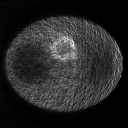

As shown in figure 2,

the mean images for the two data sets are clear visually, while

those reconstructed by the classic EM algorithm are dominated by noise, especially the image for data set 2 due to the low count level.

Thus, we use the mean square error (MSE) between the estimation and the mean